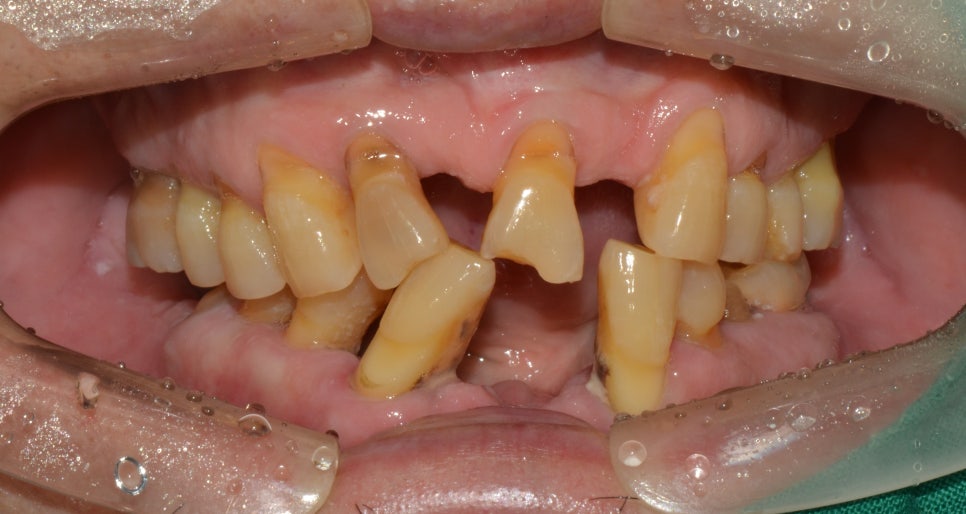

치료 전

2019년 7월 29일 (8개월 소요)

내원 이유

70대 남성분이였으며 치료를 받기 전 사진을 보시면 상실된 부분도 있으면서 위와 아래의 맞물리는 교합 상태도 좋지 않았습니다. 치아가 저작력을 내기 위해서는 윗니와 아랫니의 맞물림으로 인해 부셔주는 힘을 얻었는데요. 이러한 맞물림도 제대로 되지 않으면서 위에서 말씀드린 것과 같이 치아가 흔들리는 증상 또한 느끼고 있는 상태였기 때문에 식사를 하는것에 있어 불편함을 많이 느끼셔서 치료를 위해 내원을 해주셨습니다.